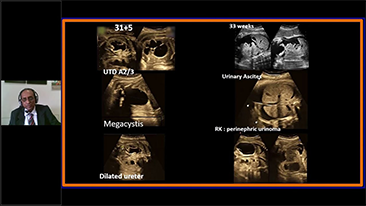

Supportata dalla piattaforma avanzata ZST+, la gamma completa di soluzioni smart di Nuewa ├© progettata appositamente per migliorare la salute della donna durante il periodo pre-gravidanza, la gravidanza e il recupero post-parto, per fornire diagnosi complete ed efficaci e per rispondere a sfide cliniche sempre pi├╣ impegnative.